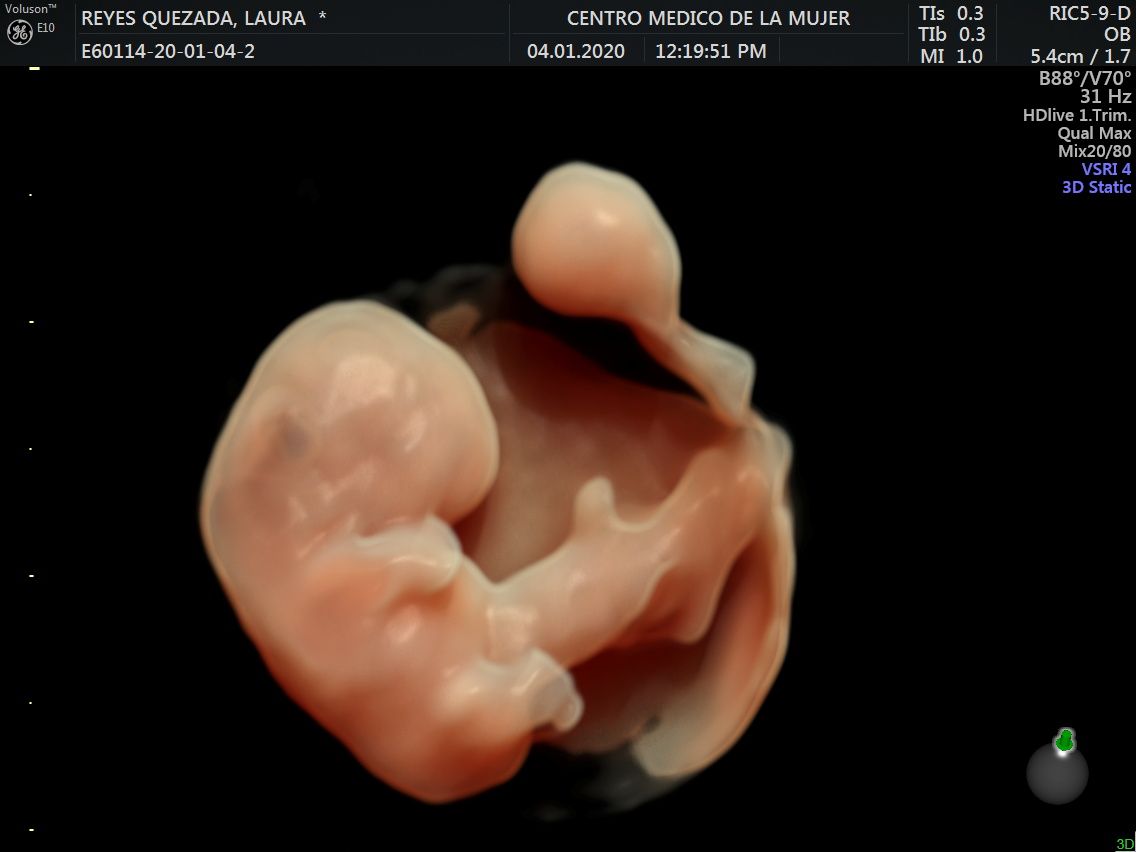

Fotos y videos

ECO Anatómico

Consiste en la evaluación especifica de cada organo y sistema del bebé con medidas detalladas de cada parte para evaluar su crecimiento proporcional.